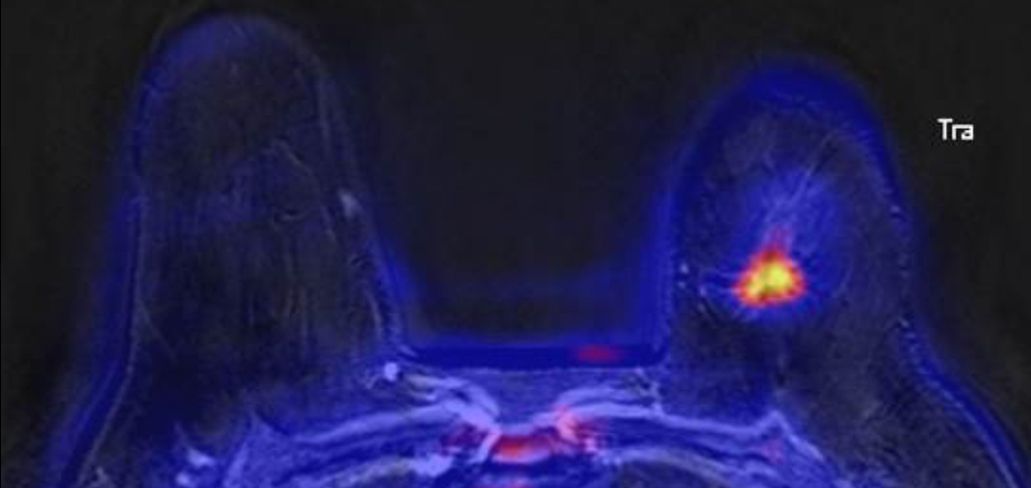

PET/MRT-Mammographie